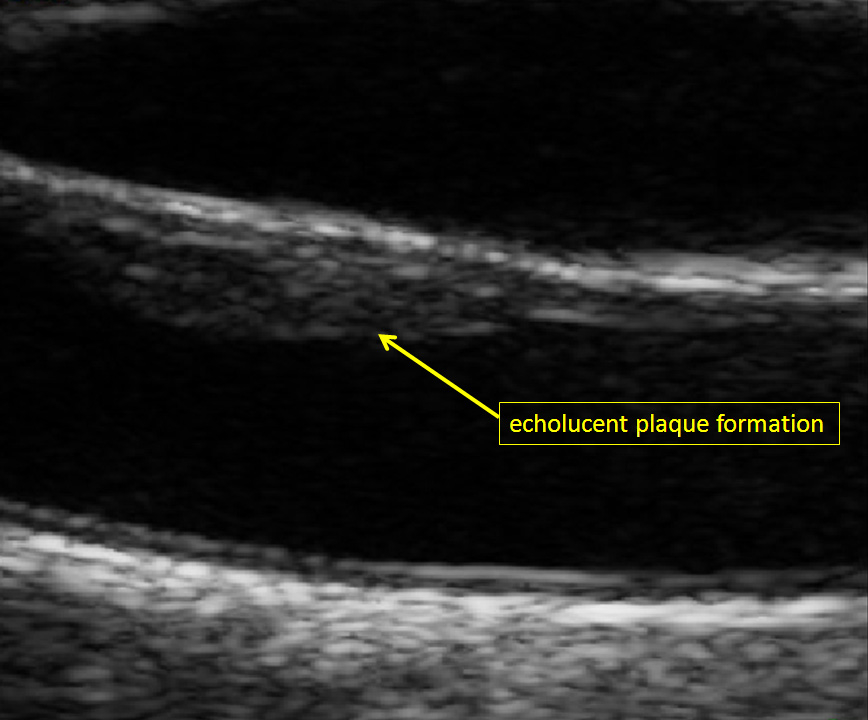

Figure 2

Echolucent carotid plaque formation at the near wall of the right common carotid artery (male study participant of the population-based Heinz Nixdorf Recall study) [19].

Atherosclerosis is a systemic and chronic inflammatory disease, which may cause cardiovascular disease, the most frequent cause of death in the world [2]. A long term thesis in the development of atherosclerosis was the “response-to-injury” theory [3], in which a physical injury of endothelium was considered to be responsible for atherosclerotic changes of vessel walls. This view was completed in the last three decades, since endothelial dysfunction was considered to be a functional trigger [4, 5]. Briefly, the infiltration of LDL-cholesterol through the endothelium, LDL-deposition in the intima and the following oxidative and enzymatic processes have been described [6]. Hence, the intima-media complex of arterial walls plays an essential role in the pathogenesis of atherosclerosis and may reflect different stages in the development of the disease: a hypertensive hypertrophic response of medial cells can be observed in early phases of atherosclerosis (quantified by CIMT-measurement), while carotid plaque formation are often seen in later stages of atherosclerosis, which may be caused by inflammation, oxidation, endothelial dysfunction, and/or smooth muscle cell proliferation [7]. An increased CIMT is typically seen at the CCA, while carotid plaque formation are more frequent at the CB or ICA. Plaque formation at the CB or ICA are more associated with hyperlipidaemia and MI, while an increased CIMT at the CCA shows a stronger relationship to hypertension and stroke [8].

The last three decades, quantification and evaluation of carotid plaque formation has changed remarkably. In addition to cursory assessments like degree of stenosis and echogenicity, other distinctive features have been used to investigate carotid plaques. The most common used criteria for plaque investigation are echogenicity (echolucent, echogenic, mixed echogenicity), echogenic distribution pattern (homogeneous versus inhomogeneous) and evaluation of surface structure (regular versus irregular). Furthermore, measurement of two dimensions (2D) and three-dimensions (3D) are used to quantify total plaque area and total plaque volume [53, 54]. Lastly, plaque vascularisation on contrast-enhanced ultrasound are developed to optimise cardiovascular risk prediction [55, 56]. Because the prevalence of carotid plaques in a population at 60 years is 60%–90% [57] it seems to be of additional benefit for risk prediction to take this different ultrasound derived pattern into consideration at least in an elderly population. Finally both, quantification of CIMT and carotid plaque formation provide different information of the atherosclerotic status and burden in the carotid artery. Taken together these two parameters have been shown to result in a superior risk prediction for coronary heart disease than with one of the parameters alone [15].